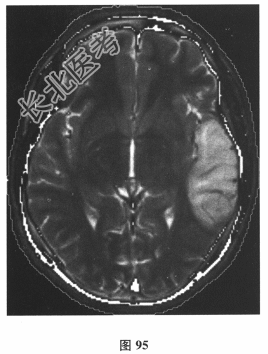

- [材料题] 患者男,24岁。由于“反复发作性四肢抽搐3个月,言语困难1d”到院就诊。3个月前饮酒后出现四肢抽搐、意识丧失,持续3min左右自行缓解;10d前再发一次四肢抽搐。遂行颅脑CT(图94)及MRI平扫检查(图95)后予丙戊酸钠对症治疗。1d前再发四肢抽搐,出现言语困难。其母亲有糖尿病病史。查体:身材矮小,意识清楚,感觉性失语,四肢肌力、肌张力正常,腱反射对称活跃,深、浅感觉正常,病理反射未引出,脑膜刺激征(-)。脑脊液:压力110mmH₂O,细胞、蛋白、葡萄糖、氯化物均正常,乳酸3.6mmol/L↑。